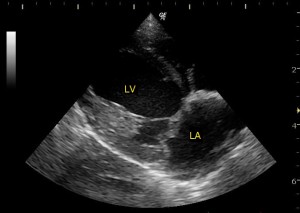

正常な心臓の超音波画像です。

LA が左心房で、LV が左心室です。 血液は LA から LV に一方通行に流れます。